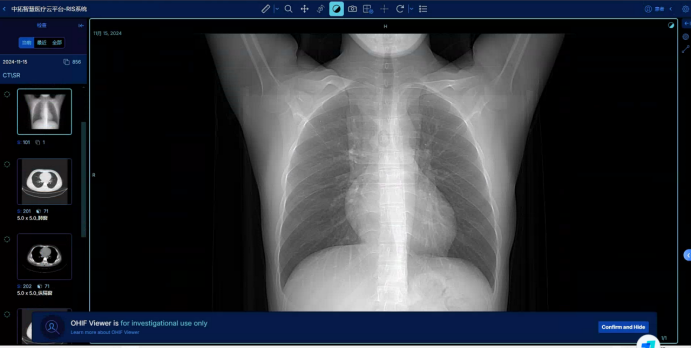

3、醫療資源共享中心:統籌建立縣域內醫學檢驗、醫學影像、心電診斷、病理診斷等資源共享中心,提高資源配置和使用效率。

影像數據中心